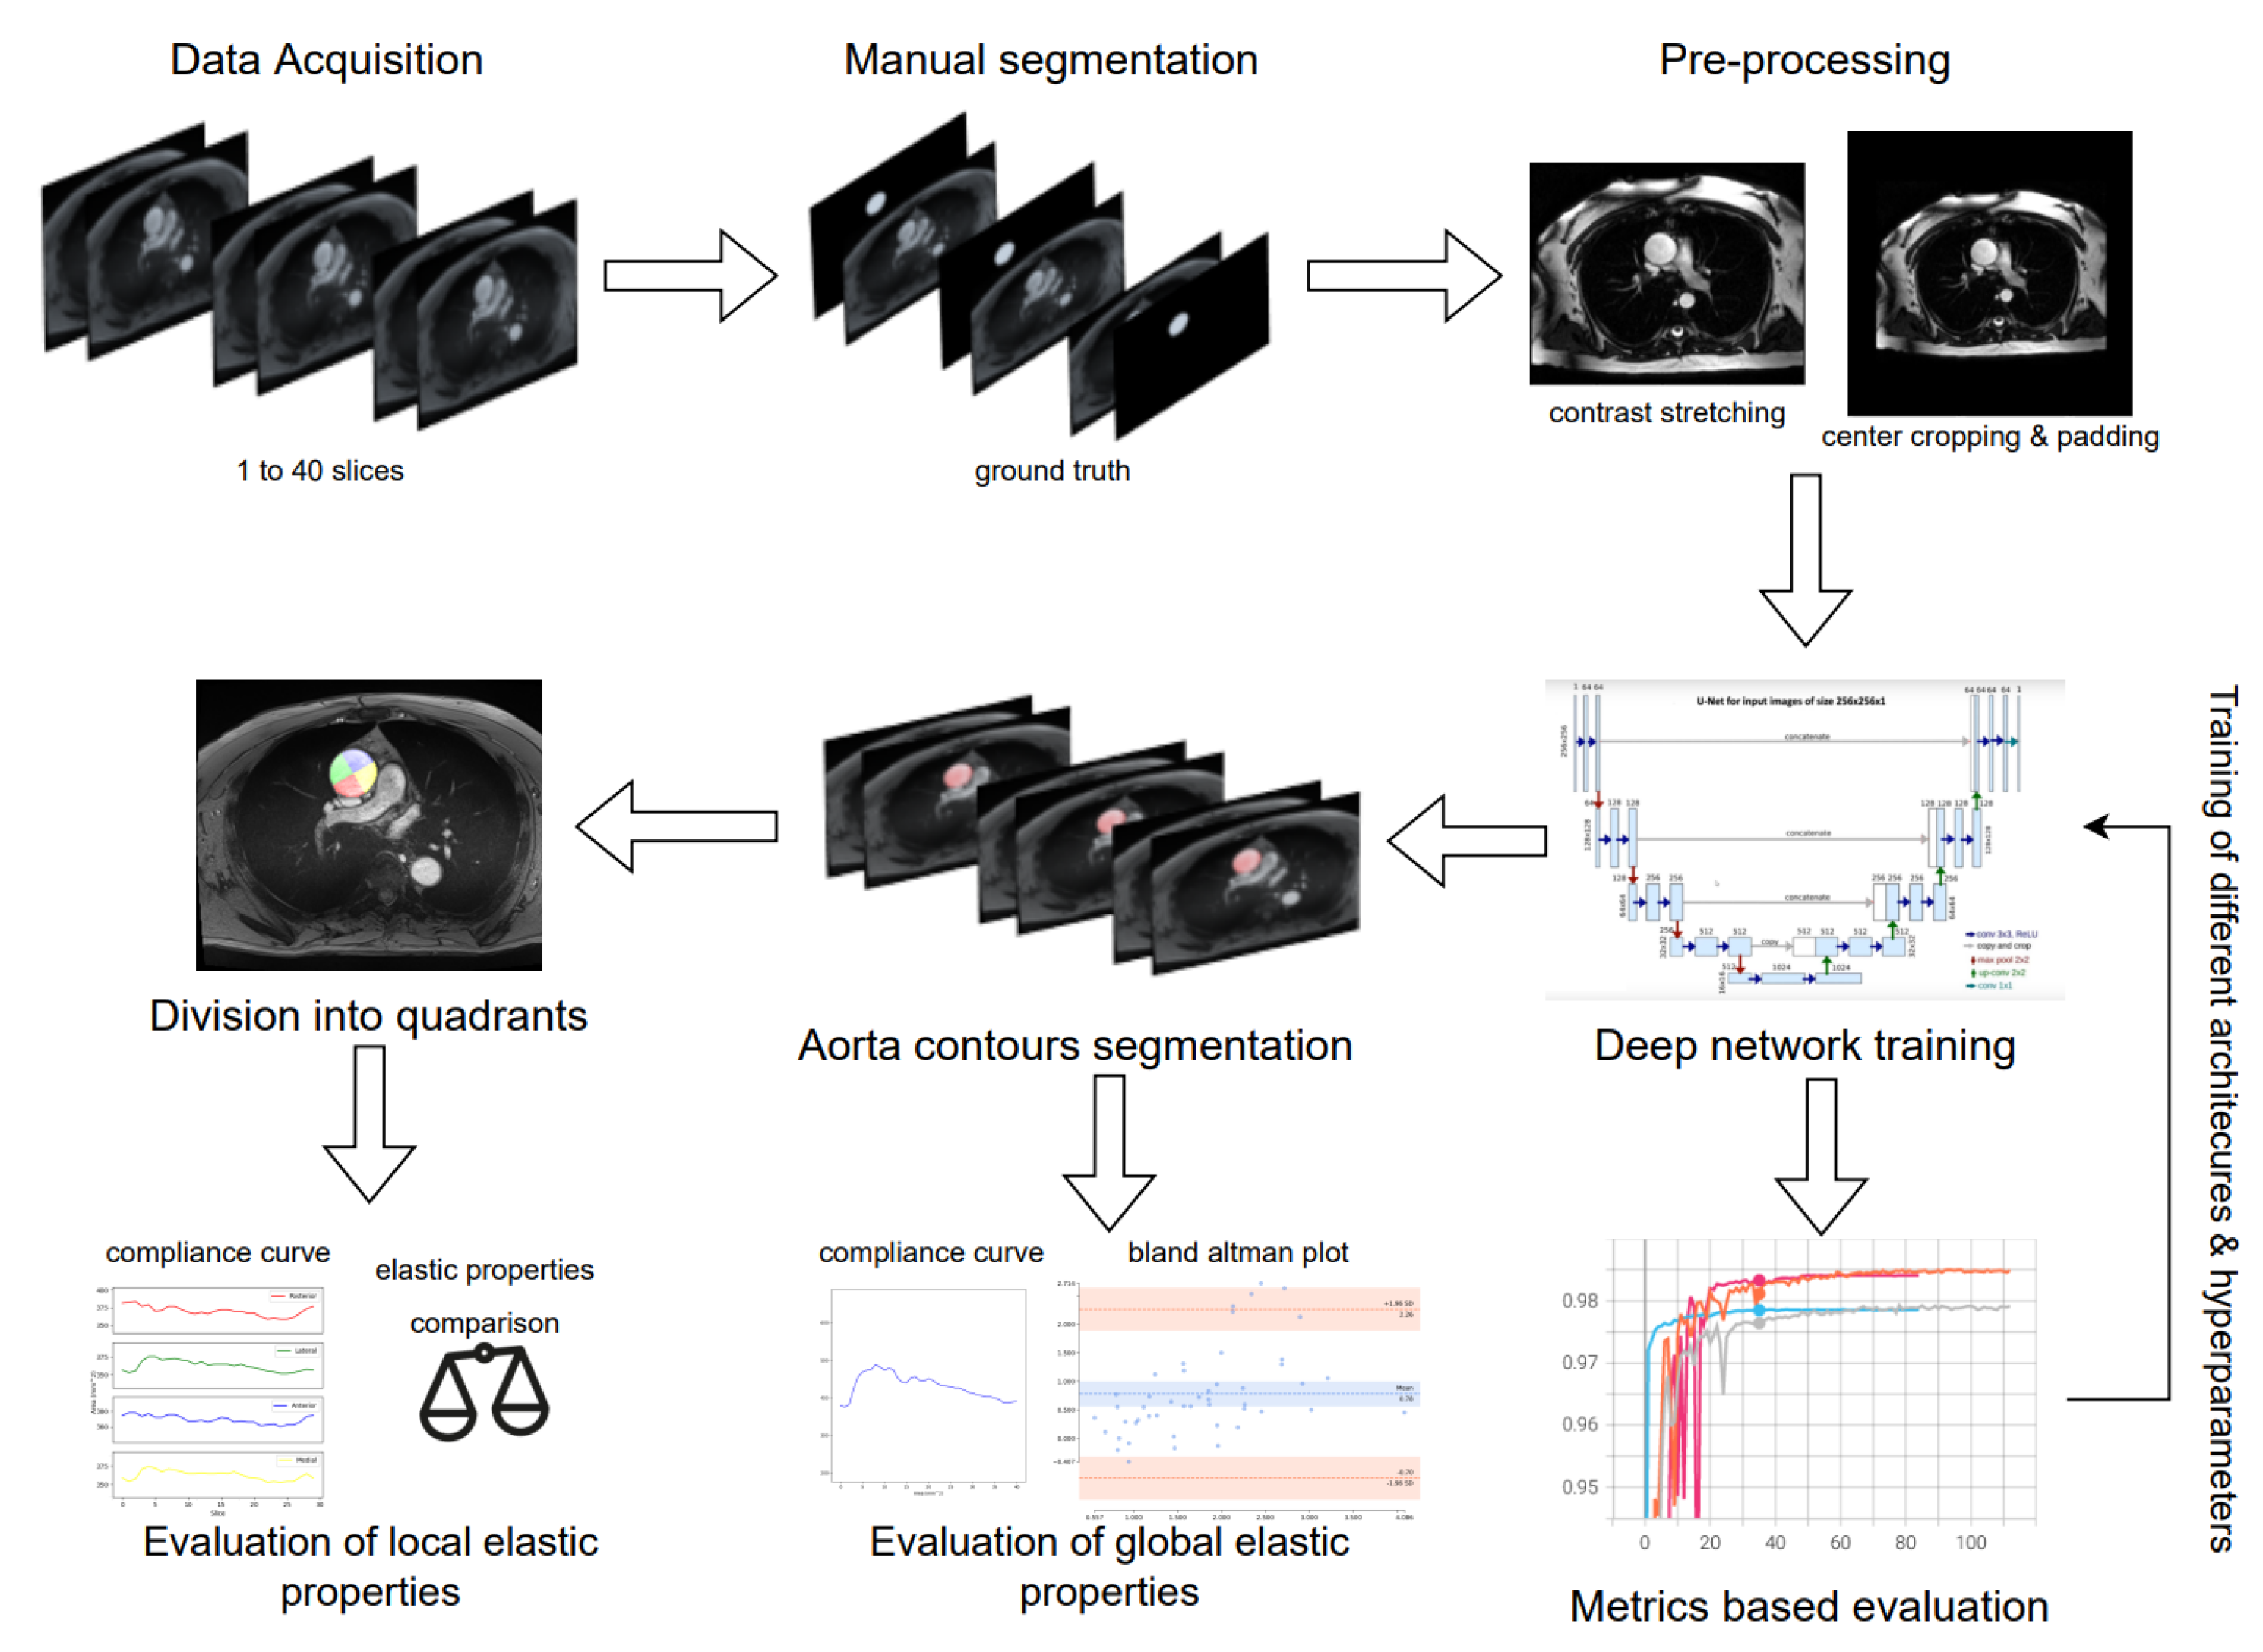

2.4. Deep Learning Segmentation and In-Vivo Elasticity Assessment

2.4.1. Preprocessing

2.4.2. Data Augmentation

2.4.3. Fully Convolutional Networks and U-Net

2.4.4. Training

3. Results

3.1. Evaluation of Deep Learning Models

3.2. Global Elastic Properties’ Evaluation

3.3. Local Elastic Properties’ Evaluation